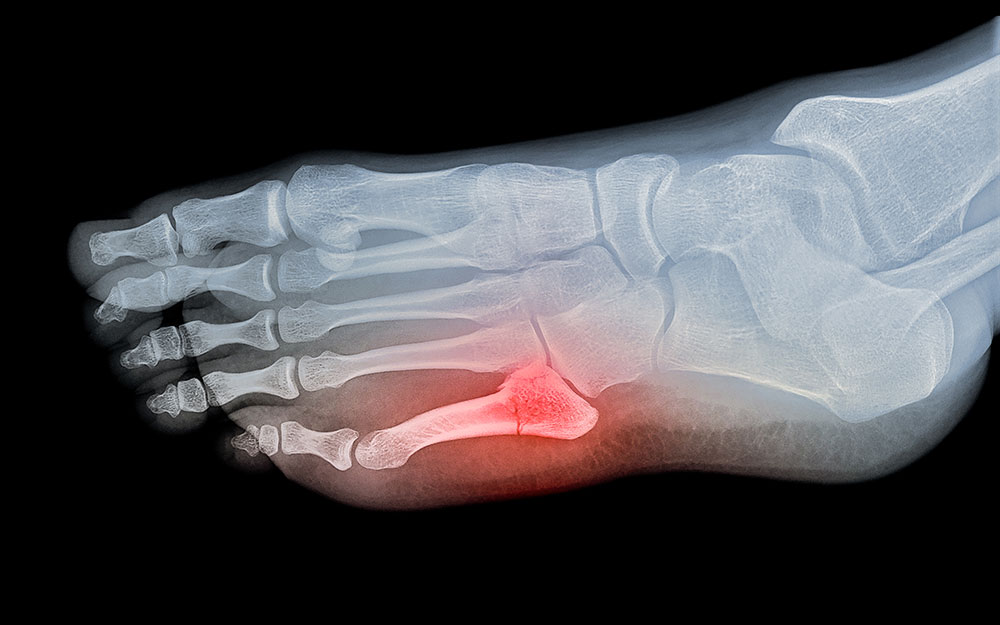

Complex Fractures (Trauma)

The structure of the foot is very complex and consists of bones, muscles, joints and other soft tissues. A fracture, which refers to a break in the bone, of the toe and foot bones may thus cause a serious injury, if not treated immediately. Traumatic toe/foot fractures are caused by a direct impact or hit to the toe or foot. They are either non-displaced (bone stays in its position) or displaced (bone or fragments have changed position). The signs and symptoms of a traumatic fracture include a sound when the bone breaks, pain at the place of impact (may last for a few hours), visible change/deformity in the toe appearance, and bruising or swelling at the next day. While not all fractures require surgical treatment, it is important to get any fractures treated as soon as possible to avoid further complications.